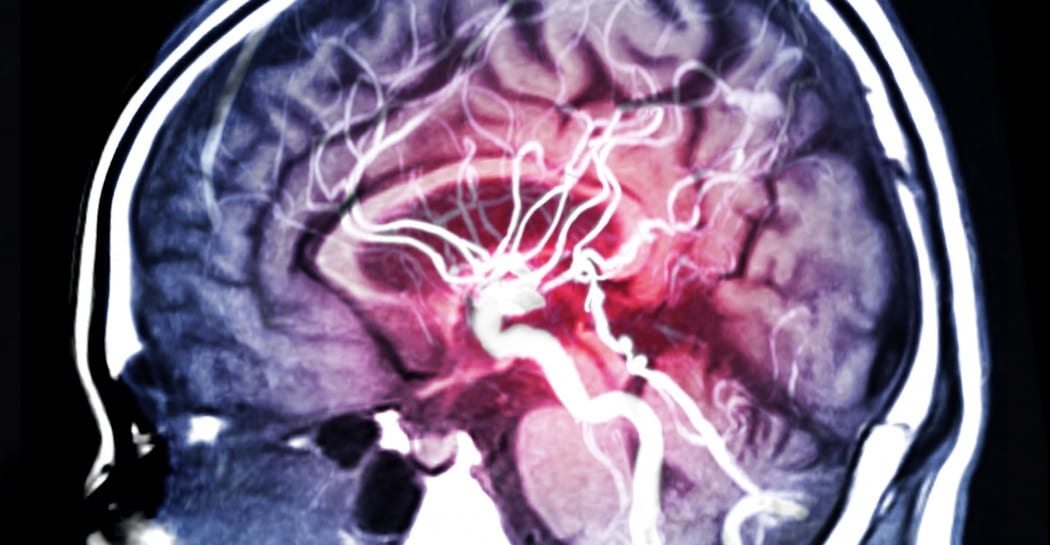

Aneurysm Awareness Month

Read more: Aneurysm Awareness MonthAn aneurysm is a weak spot in the blood vessel in the brain and over time it starts to balloon out and has the potential to rupture. Dr. Ahsan Sattar, director of Neuroendovascular Surgery and Stroke at Mountainside Medical Center, states the aneurysm cause is multifactorial; high blood pressure, smoking, family history of brain aneurysms,…